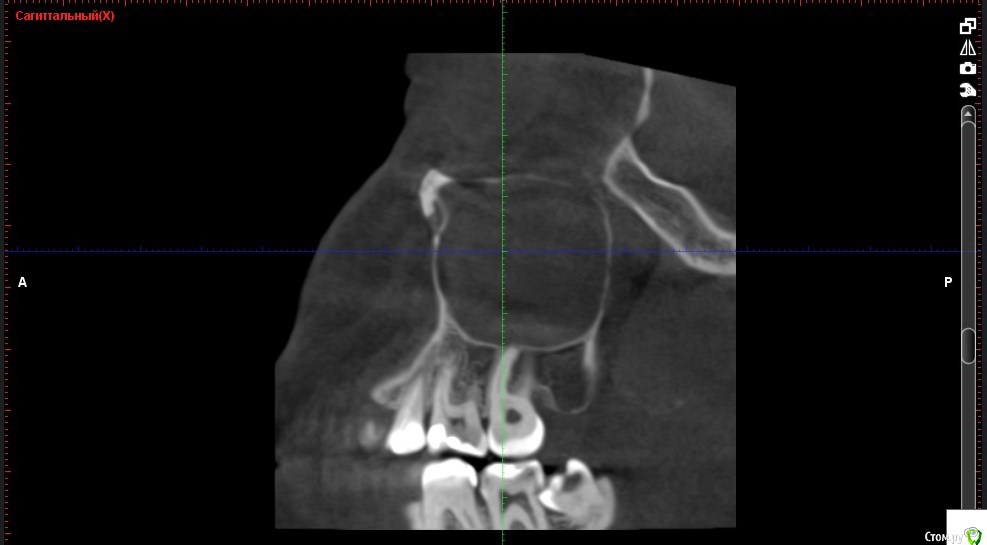

Verasss Опубликовано 8 октября, 2016 Автор Поделиться Опубликовано 8 октября, 2016 КТ от 08.09. Извините, что в таком виде, надо менять ОЗУ. Ссылка на комментарий

DmitrySH Опубликовано 8 октября, 2016 Поделиться Опубликовано 8 октября, 2016 В таком виде КТ малоинформативно. Но гайморита нет. Ссылка на комментарий

Verasss Опубликовано 28 октября, 2016 Автор Поделиться Опубликовано 28 октября, 2016 Добрый вечер! Ещё раз попытаюсь прикрепить скриншоты КТ от сентября. Если качество совсем не устраивает, подскажите, пожалуйста, какие сделать снимки?К сожалению, программа не позволяет вывести снимки на полный экран и заскриншотить в более хорошем качестве. Ссылка на комментарий

Verasss Опубликовано 28 октября, 2016 Автор Поделиться Опубликовано 28 октября, 2016 еще снимки Ссылка на комментарий

Verasss Опубликовано 28 октября, 2016 Автор Поделиться Опубликовано 28 октября, 2016 и еще Ссылка на комментарий

Verasss Опубликовано 23 ноября, 2016 Автор Поделиться Опубликовано 23 ноября, 2016 Сделала ещё 1 кт, спустя почти 2,5 месяца после первого. Посмотрите, пожалуйста, есть ли изменения? Напомню, что пункцию гайморовой мне сделали. Ссылка на комментарий